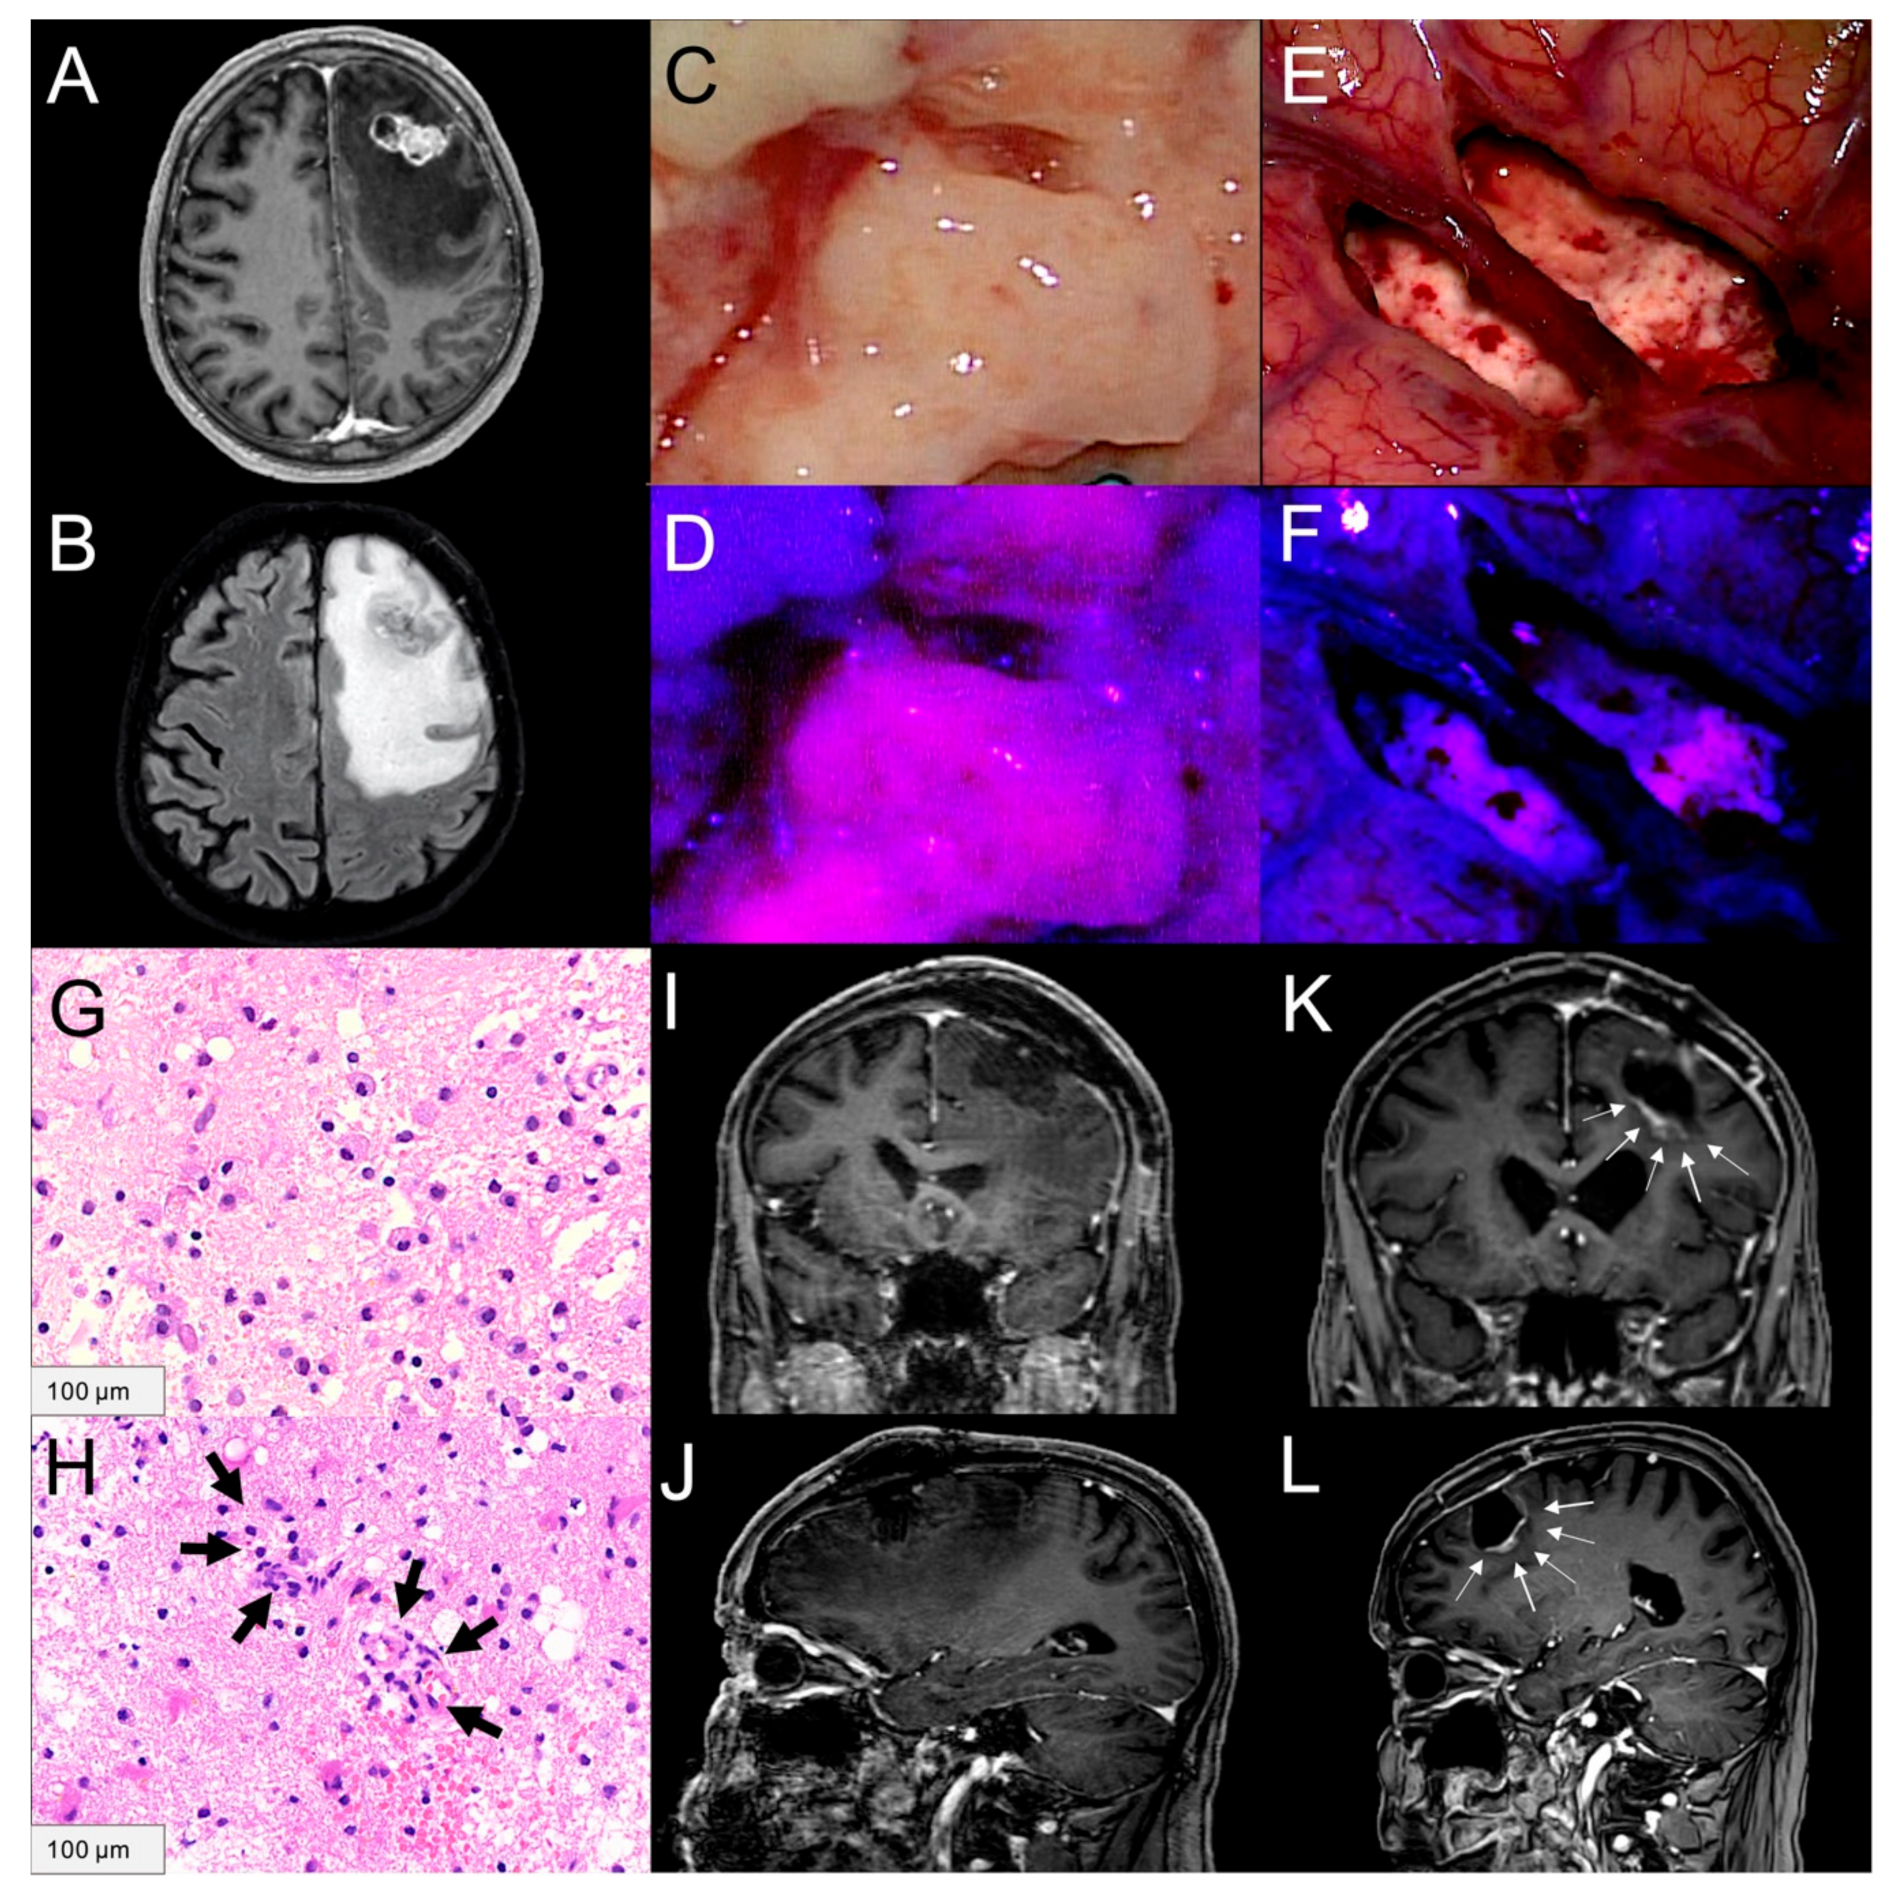

2.3. 5-ALA Fluorescence Characteristics of Peritumoral Brain Tissue

2.4. Tissue Samples from Peritumoral Brain Tissue and Histopathology

2.4.1. Tumor Cell Infiltration

2.4.2. Angiogenesis

4.3. Histopathological Assessment